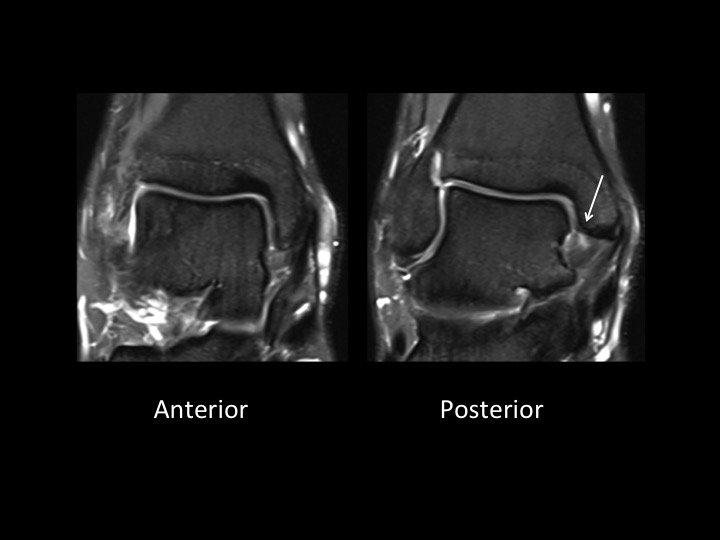

28M basketball injury 6mos ago with pain and tenderness in region of tibialis anterior at anteromedial ankle

This is an uncommon form of ankle impingement characterized by osteophytic spurring at the anterior medial malleolus and adjacent capsular/synovial proliferation and inflammation. The red arrow shows both in slide 1. There is a superimposed partial tear of the posterior (but not anterior) tibiotalar (deep deltoid) ligament, which is separate from this lesion. (note the normal tibialis anterior in slide 1) Reference article.

anteromedial ankle impingement